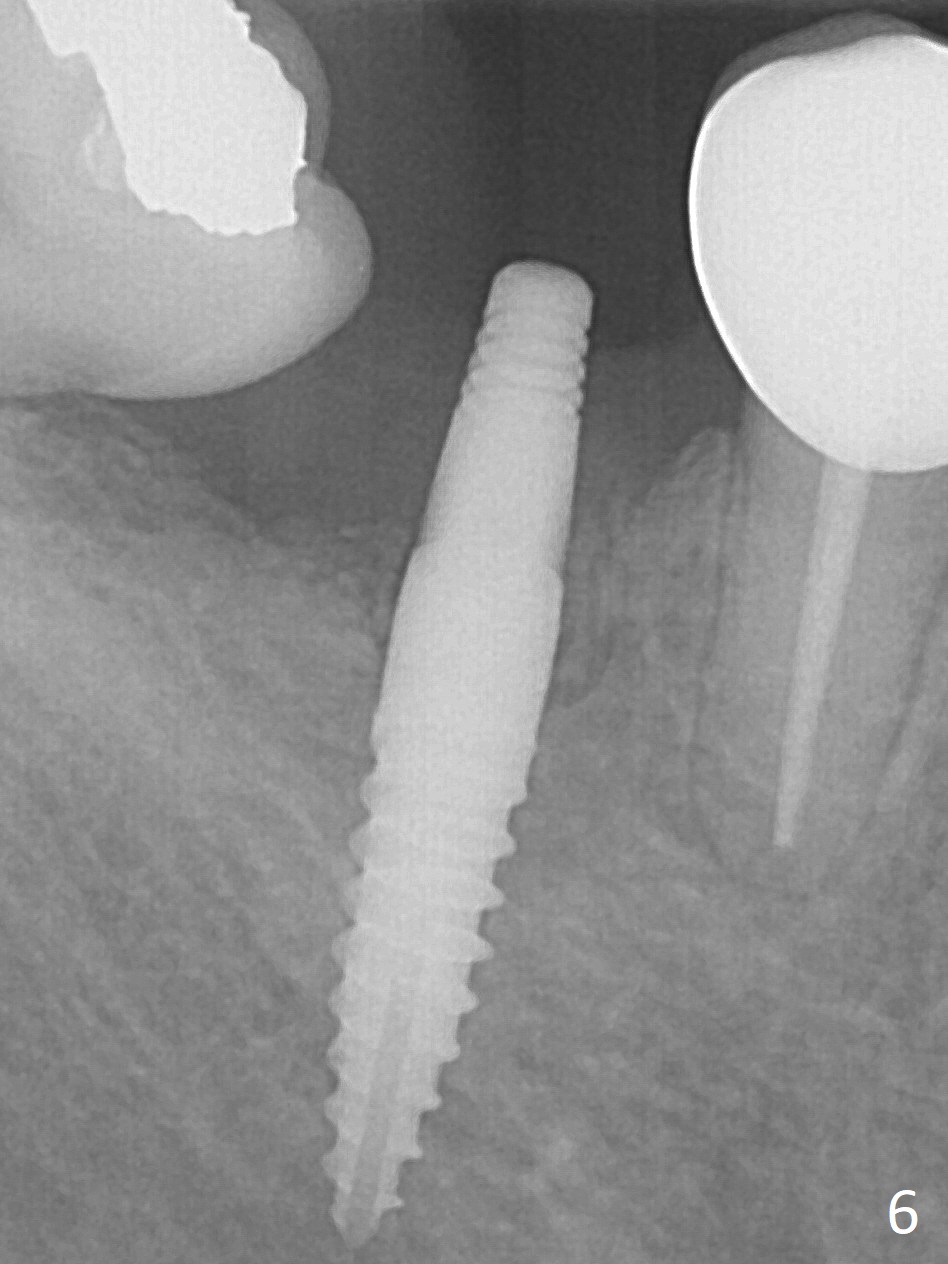

Incision reveals a narrow ridge and a narrow mesiodistal space at #30 (Fig.1).  It seems that a 1-piece implant is indicated.  Due to limited mouth opening, a 1.2 mm drill is unstable in place after use for 10 mm; instead a 1.5 mm drill is able to be inserted for 8 mm (Fig.2).  A 3x10(2) mm 1-piece dummy implant is placed with 40 Ncm at an apparently acceptable level (Fig.3 >).  Clinically a few threads are exposed buccally.  When a definitive implant with the same dimension is inserted with 45 Ncm, it looks seated too deep (Fig.4,5).  The latter is noted after suturing.  The implant is backed up for a few turns so that the length of the abutment appears a little more reasonable.  Introspectively, a 4 mm cuff should have been used after ridge reduction.  Although there is no bone loss 4 months postop (Fig.6), the abutment margin (Fig.7 arrow) is subgingival (red dashed line: gingival margin).  Diode laser is used for gingivectomy prior to impression.  The bone density around the implant increases 11 months post cementation (Fig.8 *), probably related to recurrent #18 infection.  The patient uses floss after meal.